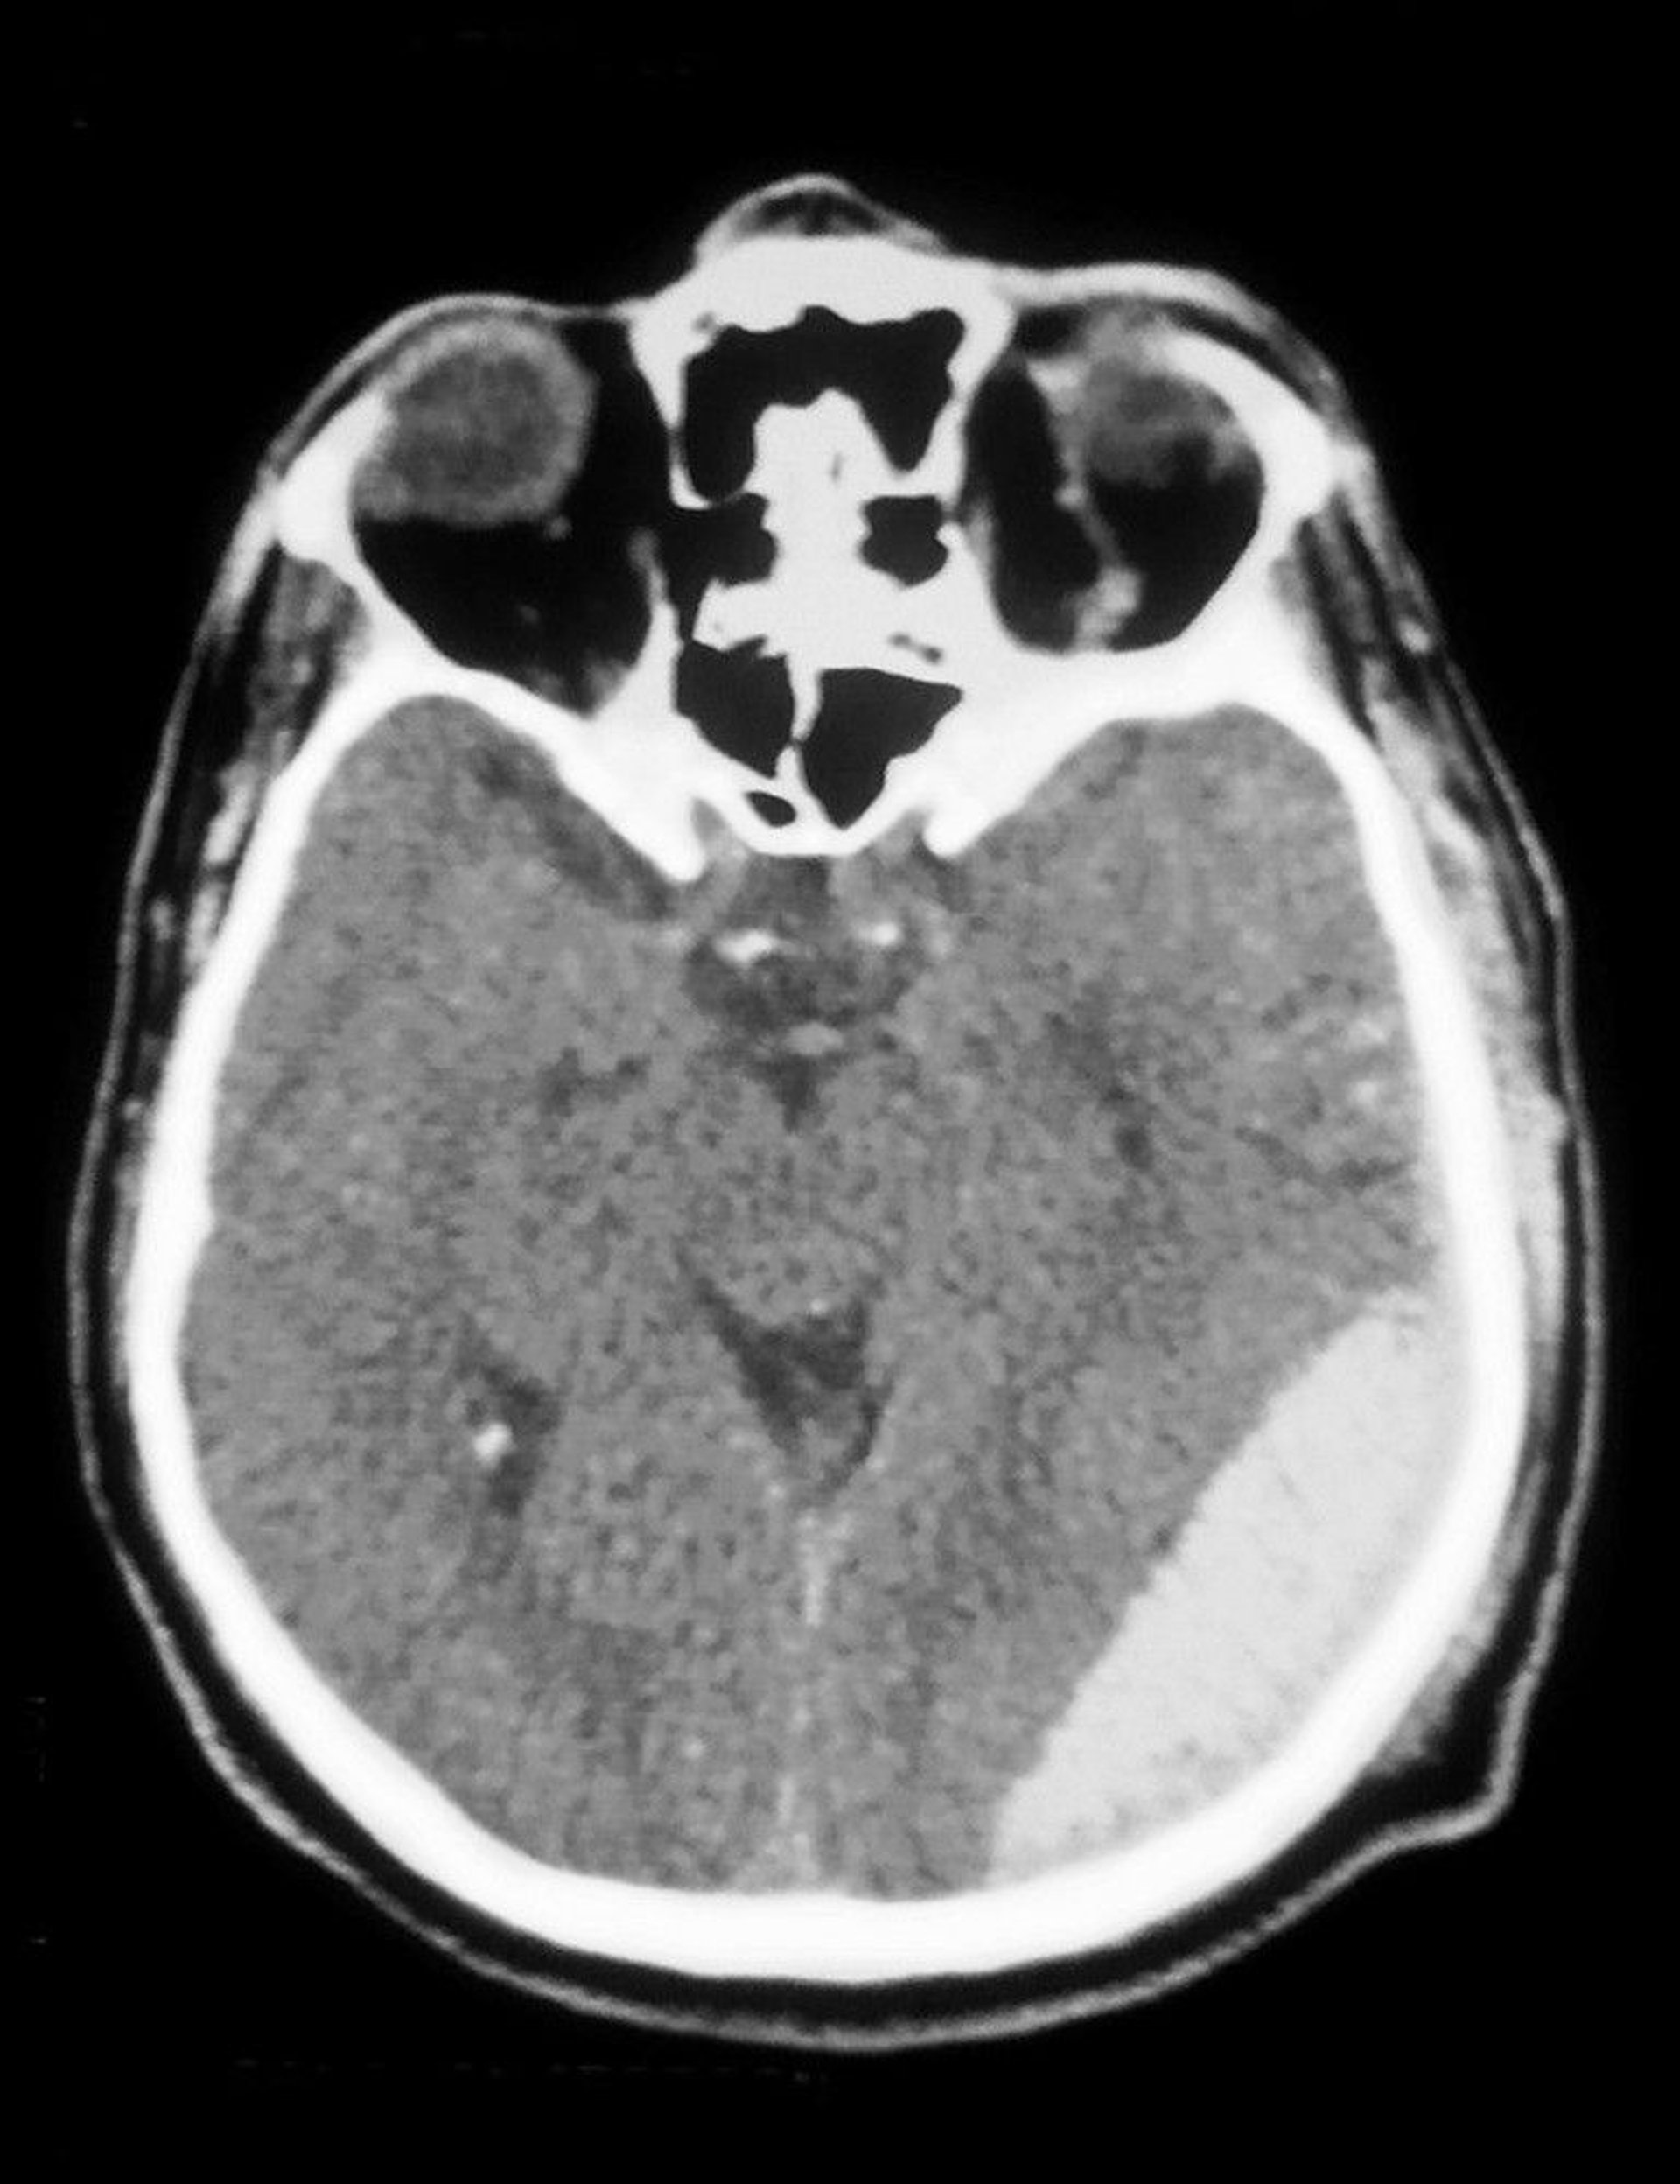

Die CT-Aufnahme zeigt ein epidurales Hämatom (Trübung unten rechts).